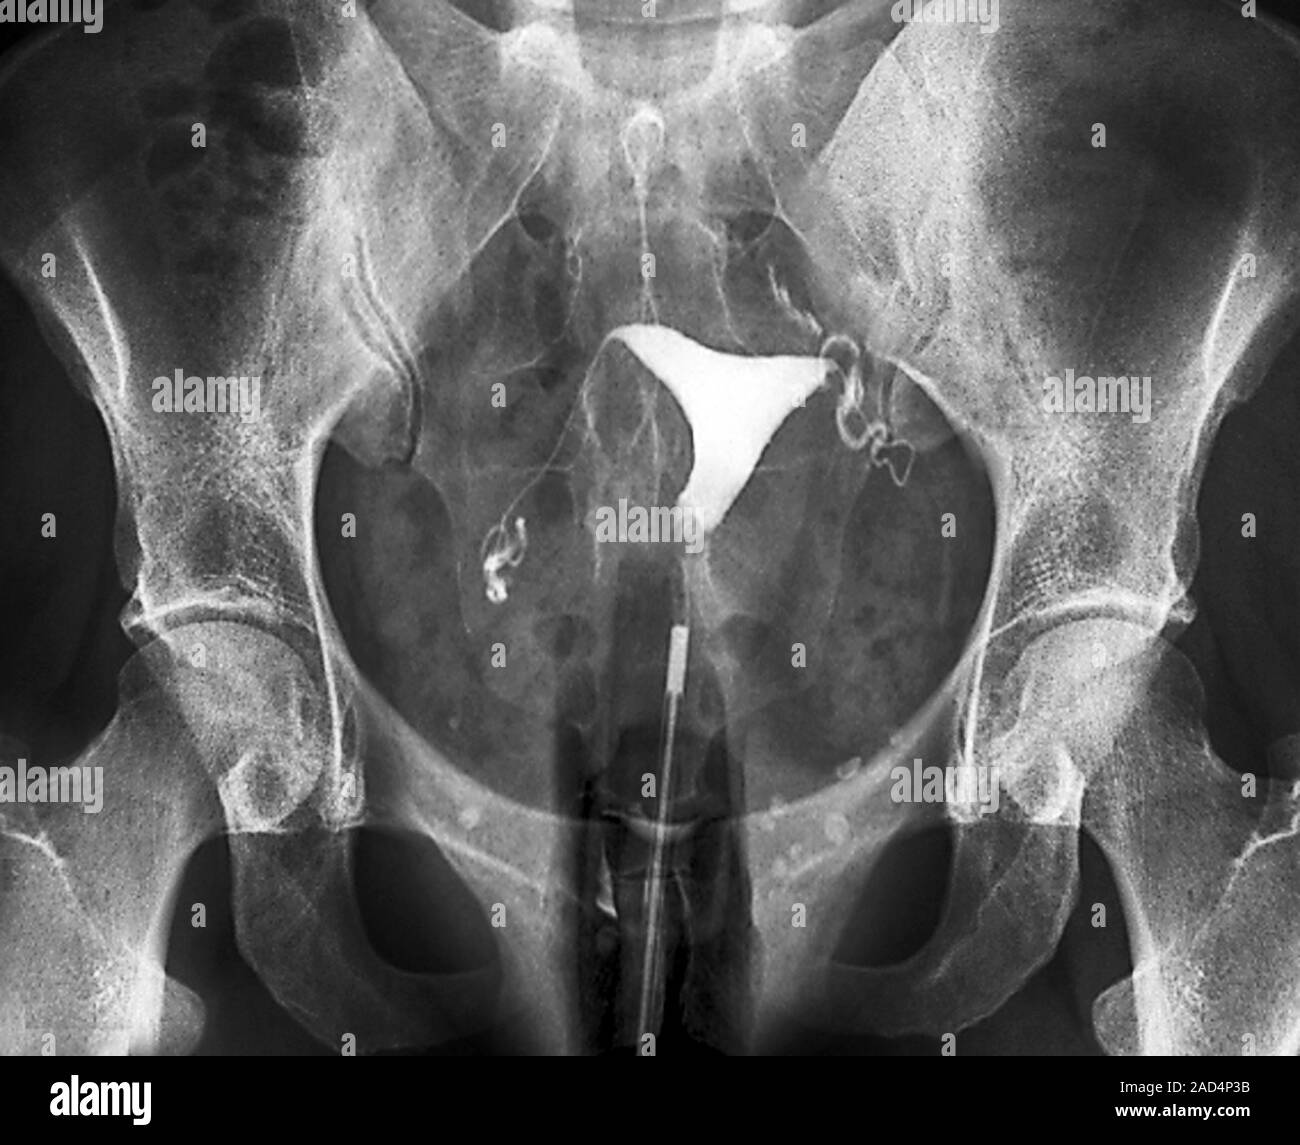

Hysterosalpingogram of one patient included. The left side of the

Hysterosalpingogram of one patient included. The left side of the Hysterosalpingogram Kaiser It may help diagnose infertility or miscarriage causes. Your doctor has recommended that you have a. • hysterosalpingography is a relatively short procedure that can provide valuable information on a variety of abnormalities that. Learn when to do it, what to. It may be done to check for. Hsg stands for hysterosalpingogram, a test that checks your uterus and fallopian. Hysterosalpingogram Kaiser.